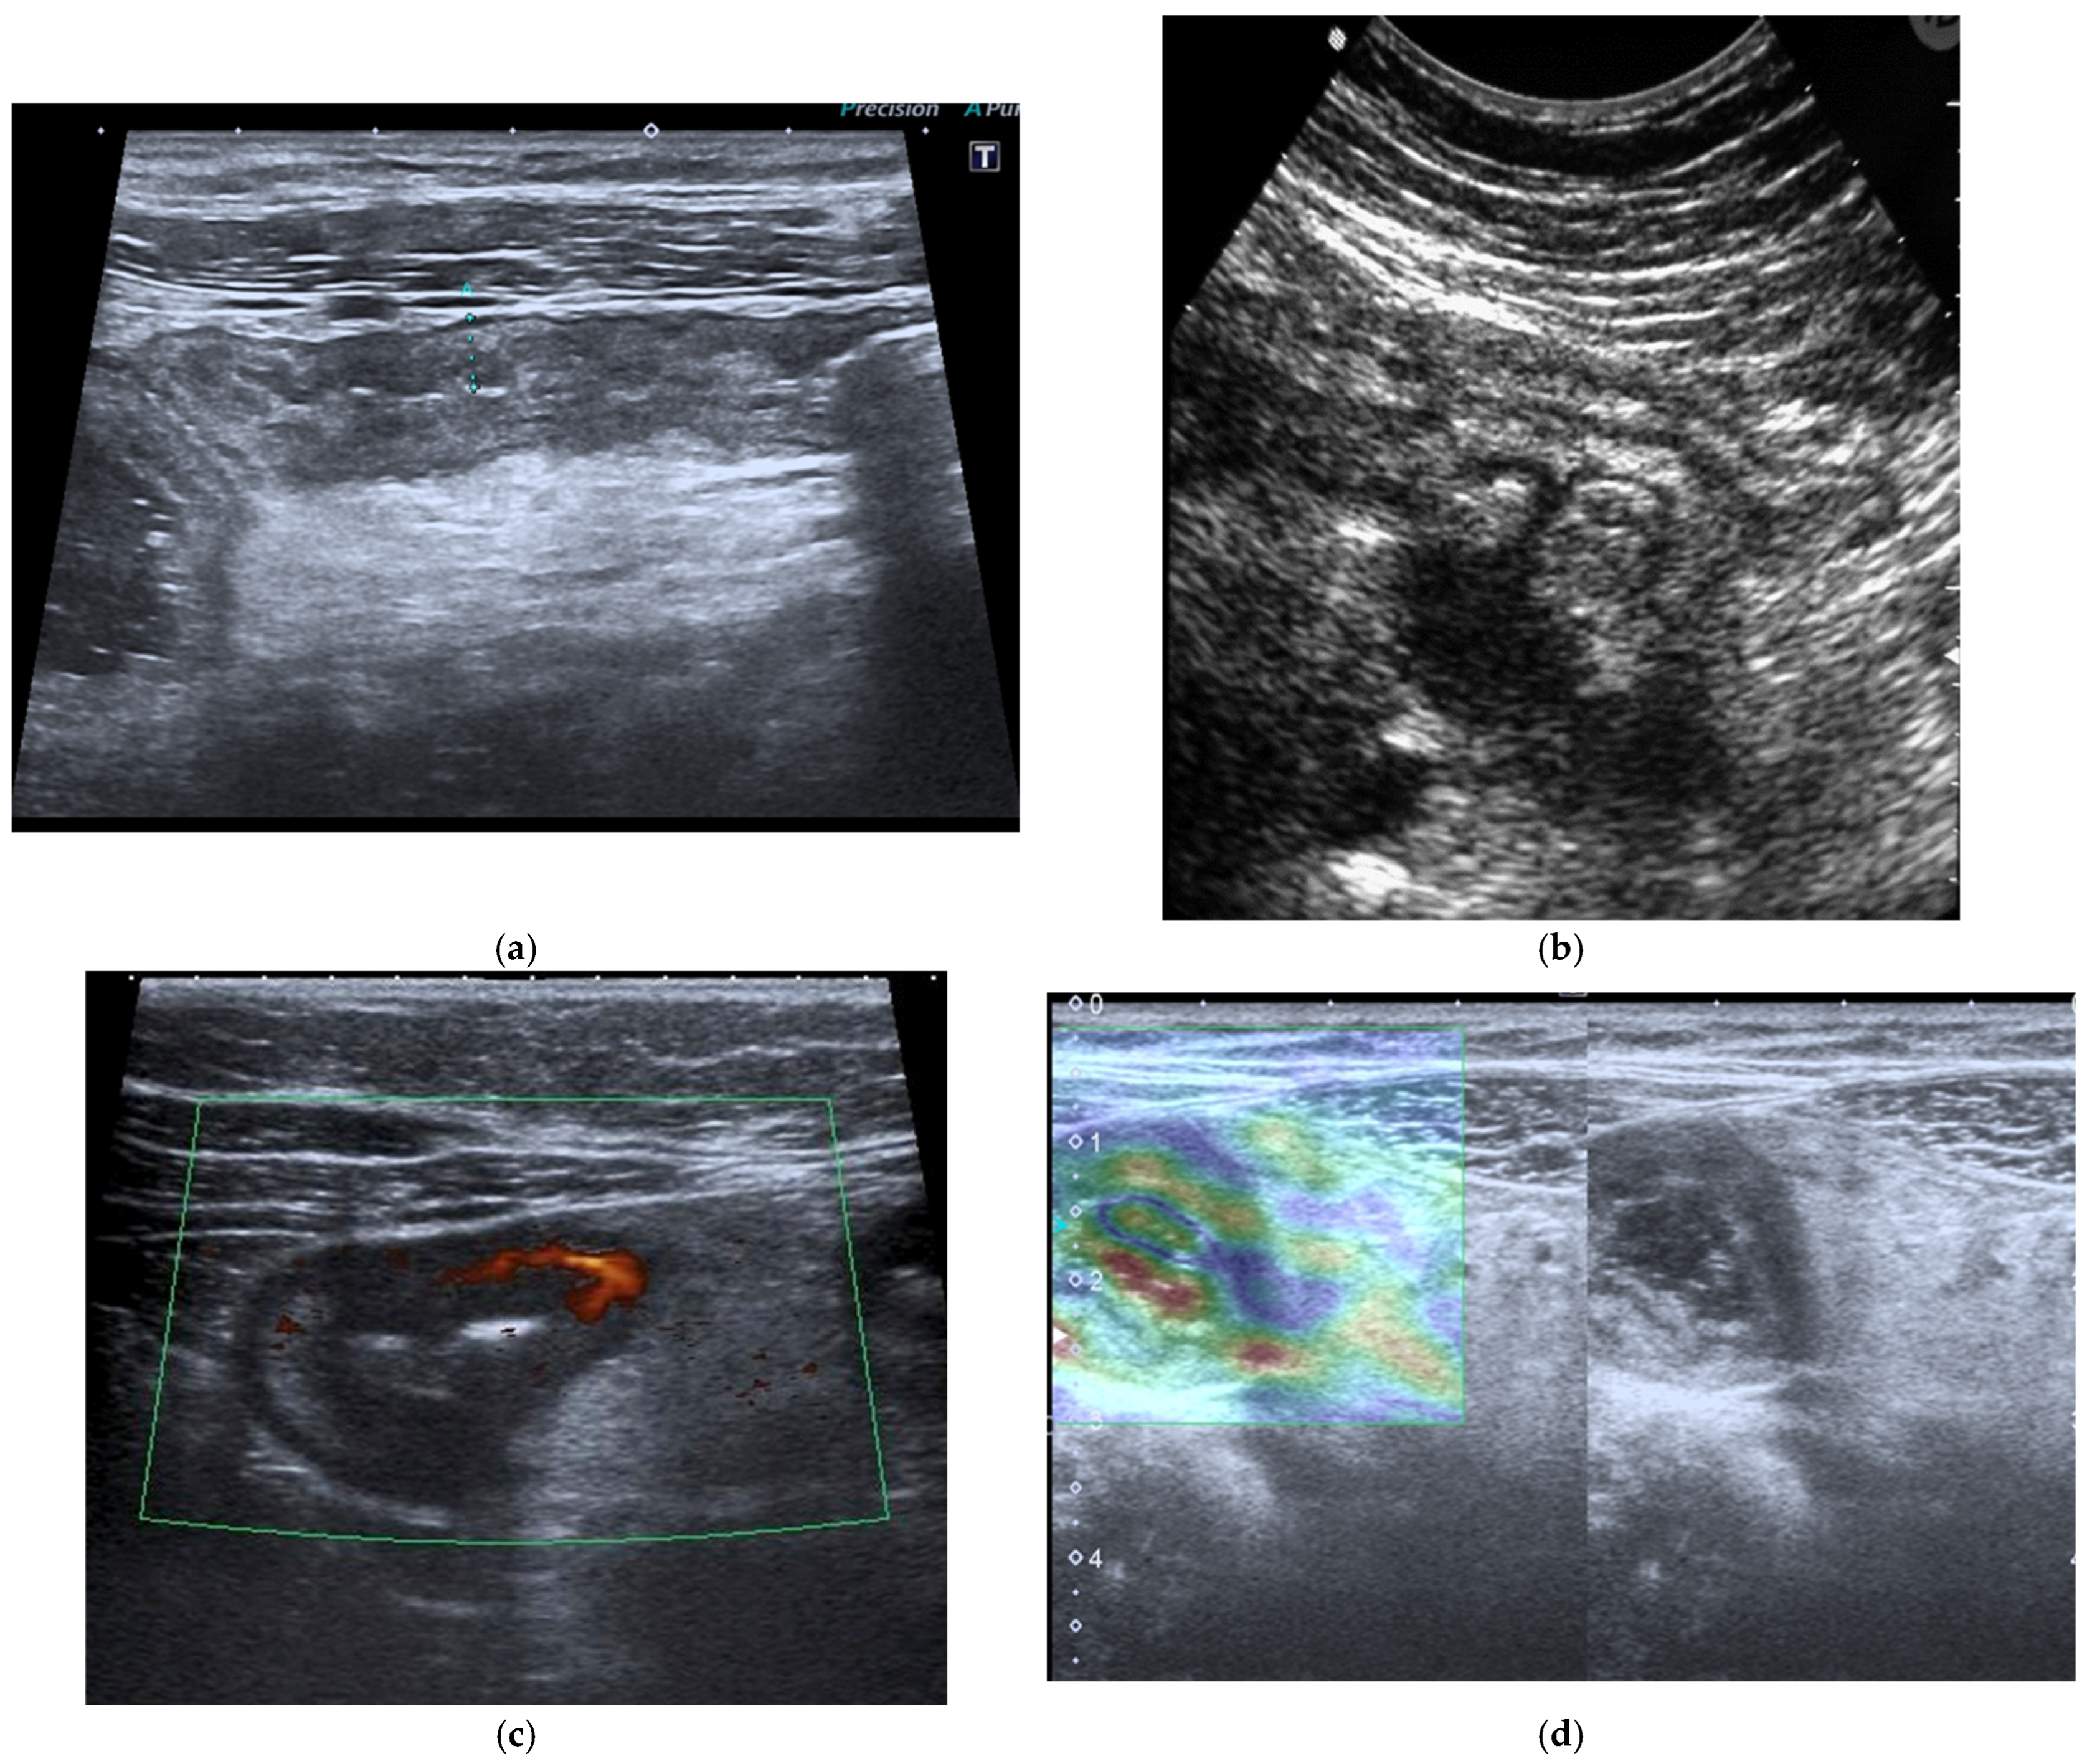

The fundamental strengths of IUS derive from its ability to visualize bowel wall thickness, mural stratification, and peristaltic activity with high temporal resolution. Bowel wall thickening represents one of the most robust markers of inflammatory activity and, when combined with color or power Doppler evaluation, ultrasound becomes a sensitive tool for assessing mural hypervascularity, considered a surrogate marker of active inflammation [33,34,35,36,37,38] (Figure 3a–c). The Milan Criteria were recently developed by the International Bowel Ultrasound Group (IBUS) and included in the latest guidelines to standardize IUS assessment of inflammatory bowel disease [38]. Contrast-enhanced ultrasound (CEUS) allows dynamic evaluation of microvascular perfusion, enabling a more refined analysis of transmural enhancement patterns. CEUS is useful for early assessment of therapeutic response as well as for the identification and characterization of abscesses. Another promising development is ultrasound elastography, which may be useful in distinguishing inflammatory from fibrotic strictures, a diagnostic challenge traditionally dominated by MRE [38] (Figure 3d).

Figure 3.

(a) IUS of the ileocecal region shows wall thickening (6 mm) of the terminal ileal loop with associated cecal wall thickening in a patient affected by CD. (b) Complicated perforating CD: IUS shows marked wall thickening of an ileal loop with multiple associated mesenteric abscesses. (c) Patients with active CD: ultrasound axial scan of the affected ileal loop, shows wall thickening and increased vascularity at Color Power Doppler. (d) Elastosonography of an ileal loop affected by CD shows marked wall thickening and mild fibrosis (yellow); please note that blue-green color is lack of fibrosis, whereas yellow and red is mild to severe fibrosis.